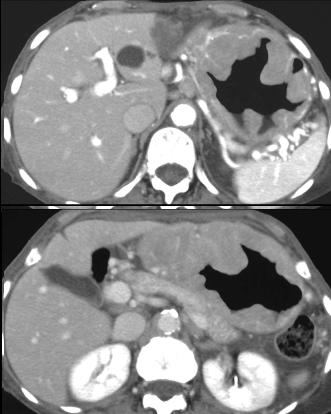

Lymphome gastrique :

Une epaississement diffuse a hypodense mais sans

stenose de l' estoma ( image TDM en coupe axiale ) .N'a

pas de rigidite a la region lesionaire |

Aspect lesionaire de

epaississement diffuse a gros plis de la muqueuse

gastrique mais n'a pas de rigidite , c'est le

caracteristique du lymphome gastrique se serve pour

diagnostic differentielle avec adenocarcinoma |